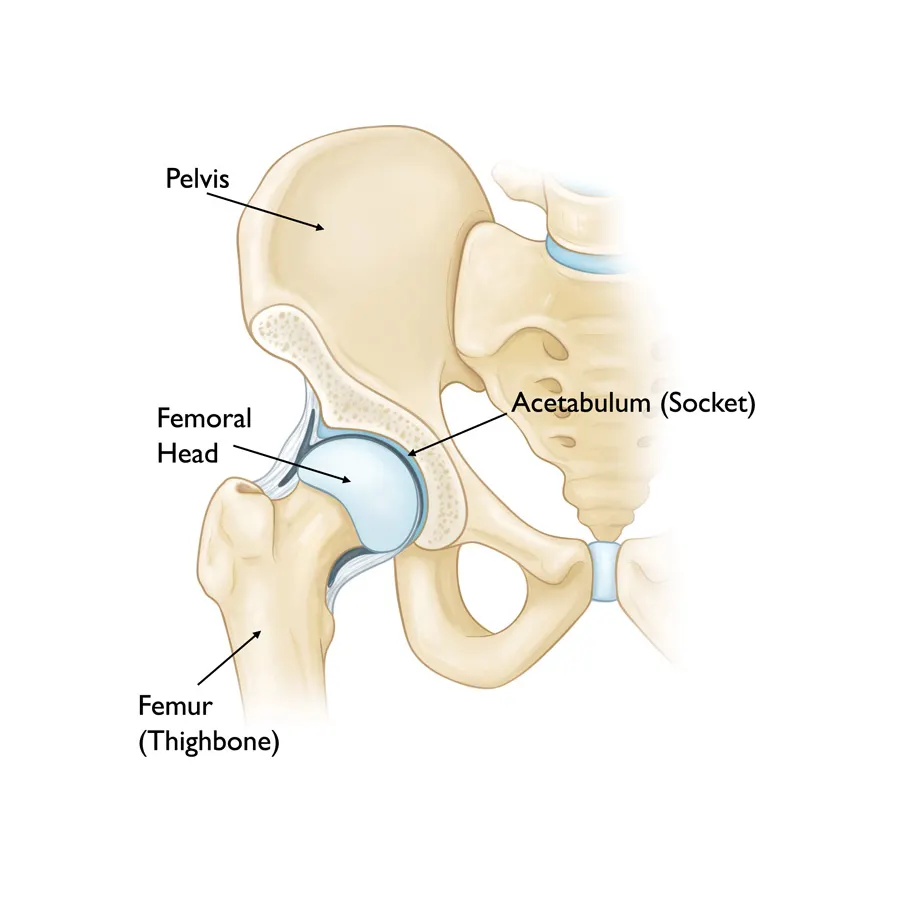

Joint Replacement

surgeries performed

Most trusted, advanced, and affordable knee, hip, elbow, limb salvage surgery in India.

Also cater to revision knee & hip replacement, post-operative care.

Dr Mujahid Saleem is an eminent Orthopaedic surgeon specialising in Joint Replacement Surgery, has exceptional Diagnostic and surgical skills operating now for over 35 years he has performed more than 20,000 surgeries using state-of-the-art techniques for optimum and functional recovery of his patients.